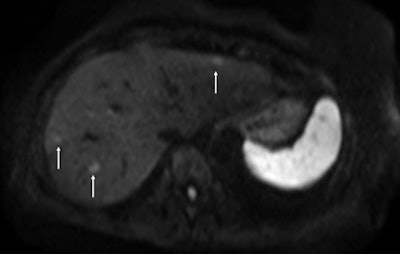

In whole-body diffusion in hematology malignancies, both anatomic evaluation and routine functional tumor imaging are increasingly combined to provide definition of tumor staging and response, said Dr. Alain Luciani, professor of radiology at the University Paris-Est Créteil (UPEC).

Current MR techniques, including respiratory triggering, phased array coils, and parallel imaging, are bringing whole-body MRI into clinical practice, especially in oncology. Ongoing national and international protocols are being developed by French academic imaging groups, and whole-body diffusion-weighted MRI is being tested as a standalone sequence compared to PET/CT for aggressive lymphoma staging and follow-up in a bicentric French-Taiwanese research program, he pointed out.

Luciani described novel instrumental developments dealing with diffusion in hematologic malignancies. For instance, combining multiple b-factor acquisitions enables the extraction of both perfusion-related and true molecular diffusion parameters, following the intravoxel incoherent motion theory.

In hematologic malignancies associated with increased angiogenesis, such as multiple myeloma, both the perfusion fraction and the true molecular diffusion parameters can be used to monitor response to treatment. This approach is currently being investigated in a public-funded French study involving hematologic and radiologic teams, further highlighting the key role of whole-body MRI in the clinical management of patients with multiple myeloma, he said.